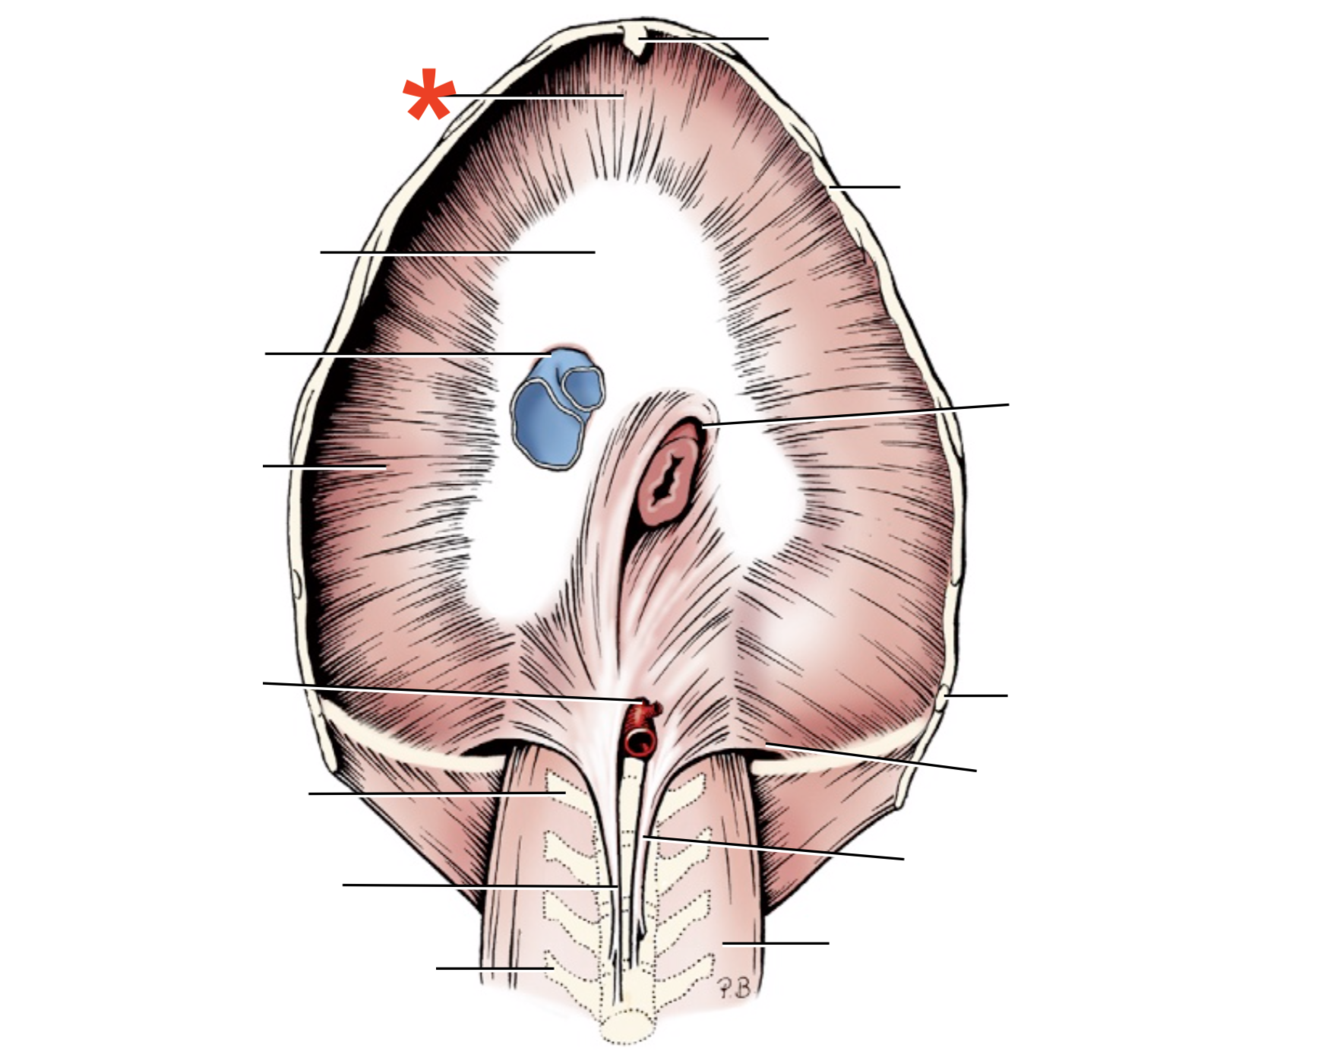

1

Q

Name given to the most cranial part of the diaphragm.

A

Cupula Diaphragmatis

2

Q

A

Pars sternalis

3

Q

A

Foramen vena cavae

4

Q

A

Pars costalis

5

Q

A

Hiatus aorticus

6

Q

A

Arcus lumbocostalis

7

Q

A

Hiatus oesophagus

8

Q

A

Crus sinistrum

9

Q

A

Crus dextrum

10

Q

A

Centrum tendineum

11

Q

A

Corona muscularis